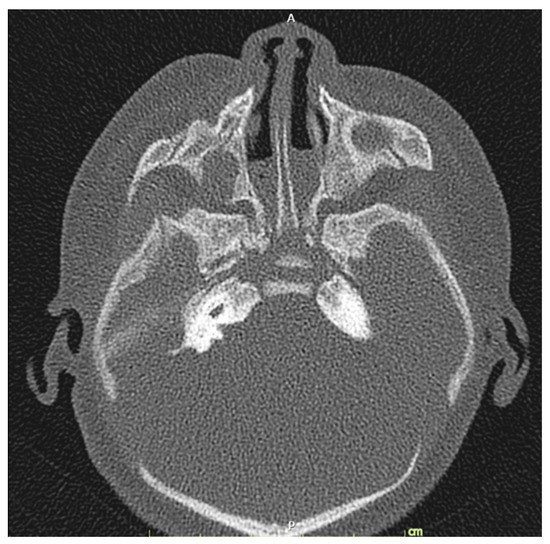

A 32-year-old pregnant woman, G4 P2102, attended her first visit of antenatal care at 23+3 weeks of gestation. Ultrasound examination for anomaly screening demonstrated cardiac defects, including double-outlet right ventricle: DORV-TOF type, with severe pulmonary stenosis (Figure 1) and left superior vena cava. Detailed ultrasound showed no associated abnormalities. Fetal biometry was consistent with gestational age except abdominal circumference and estimated fetal weight, which were relatively low (at 10th percentile), reflecting some degree of growth restriction. However, detailed ultrasound on the follow-up scans at 28 weeks of gestation showed subtle abnormalities, including malrotation of both kidneys, the hilum or renal pelvis facing posteriorly to the abdominal wall (Figure 2). Furthermore, 3D-ultrasound revealed abnormal external ear structure (markedly prominent crus of anti-helix) (Figure 3). Non-stress tests (NST) showed spontaneous fetal heart rate (FHR) accelerations (normal reactive tests) (23+3 weeks). Interestingly, the fetus showed persistent non-response to acoustic stimulation tests at 26, 30, 32, 36 and 38 weeks (no FHR accelerations as well as no quickening perceived by ultrasound) (Figure 4), probably reflective of auditory dysfunction. Based on the findings of heart defect, ear defect, renal defect and growth restriction, several differential diagnoses were listed, including CHARGE syndrome. Theoretically, fetal blood sampling for molecular genetic tests should be performed. Nevertheless, since no lethal condition was identified and the couple wanted to continue pregnancy regardless of investigation results, prenatal invasive diagnosis was avoided, and we waited for postnatal work-up instead. She had no significant underlying disease and no familial history of hereditary diseases. Her pregnancy was uneventful except that she developed gestational diabetes (GDM) at 28 weeks of gestation, which was well-controlled with diabetic diet.

Figure 1. Double-outlet right ventricle (DORV): (A) TOF type, small pulmonary artery (PA) and (B) reverse flow in the ductus arteriosis (DA) (Ao: ascending aorta; AoA: aortic arch; LV: left ventricle; RV: right ventricle; Sp: spine; VSD: ventricular septal defect).